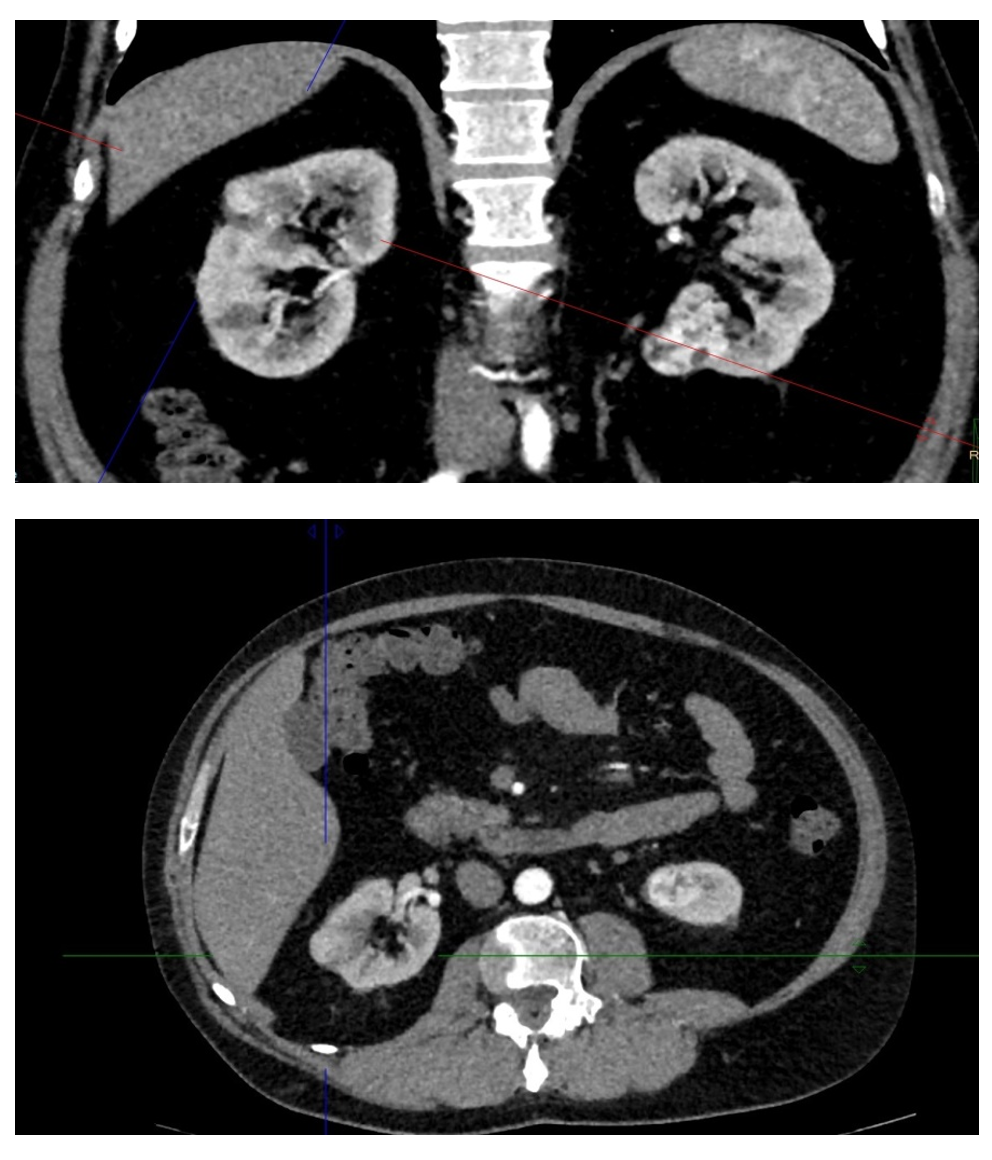

Рисунок 1 - Исходные данные

Выполнена 12.12.2024 эндоскопическая резекция левой почки на системе Da Vinci под эндотрахеальным наркозом (гистологическое заключение № 192619-30/24: в резецированной почке светлоклеточная почечно-клеточная карцинома G1, R0). В 1-е сутки послеоперационного периода показатели азотемии: креатинин 95 мкмоль/л, мочевина 6,7 ммоль/л — без клинически значимых отклонений, функция почки также без клинически значимых отклонений: СКФ 128 мл/мин. По данным узи от 13.12.2024 эхографически гематома не визуализирована. Послеоперационный период протекал без осложнений, больной выписан на 8 день.